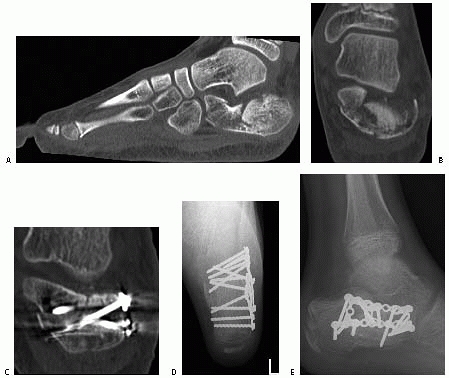

![]() |

FIGURE 27-20 Intra-articular depressed fracture of the calcaneus in a 13-year-old boy. A. Preoperative sagittal CT shows the depression of the posterior facet into the body of the calcaneus. B. Coronal CT shows the displacement of the frature fragments. C. Postoperative CT scans are useful at checking the fracture reduction and length and position of the screws. D,E. Postoperative radiographs confirm restoration of the Böhler angle.